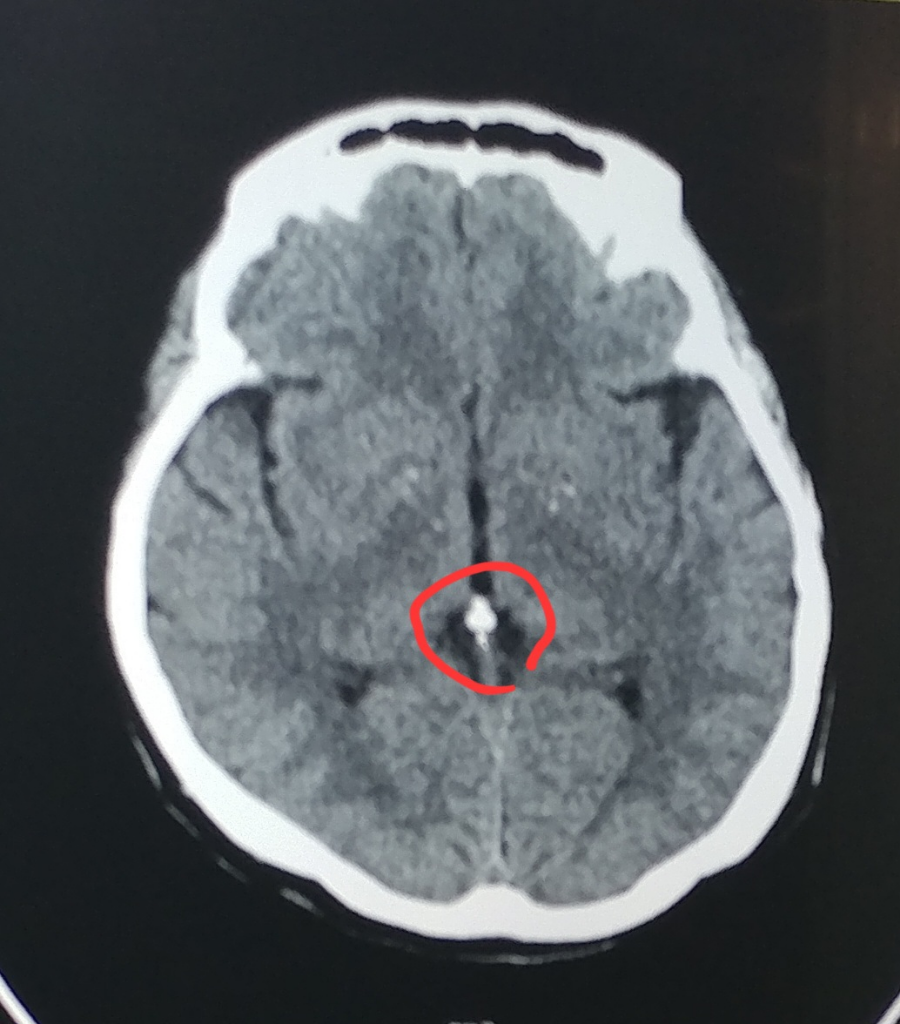

석회화가 맞습니다

MRI 사진에서도 석회화가 보이기는 하지만 CT에서만큼 분명하게 보이지는 않습니다

아래 영상은 다른 자료에서 가지고 온 것인데 CT에서 훨씬 잘 보이는 것을 확인할 수 있습니다